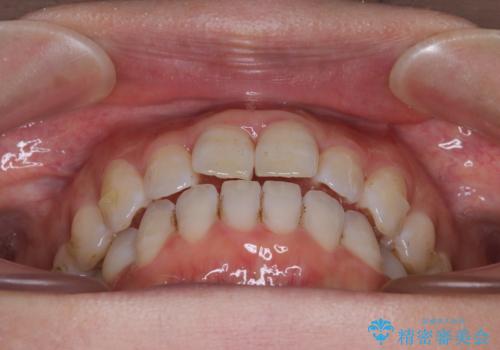

【モニター】飛び出した上顎前歯 補助装置を併用したインビザライン矯正治療

- 上下前歯が非接触となり、前方に突出していることを気にして来院された患者様です。

上下の前後差が大きいため、インビザライン単独での上顎歯列移動は困難と判断し、補助装置により上顎歯列を後方移動させ、その後インビザラインにて仕上げていくこととしました。

また、舌の突出癖が非接触の原因の大きな要因と考えられるため、舌のトレーニングをしっかり行っていくよう指導しました。